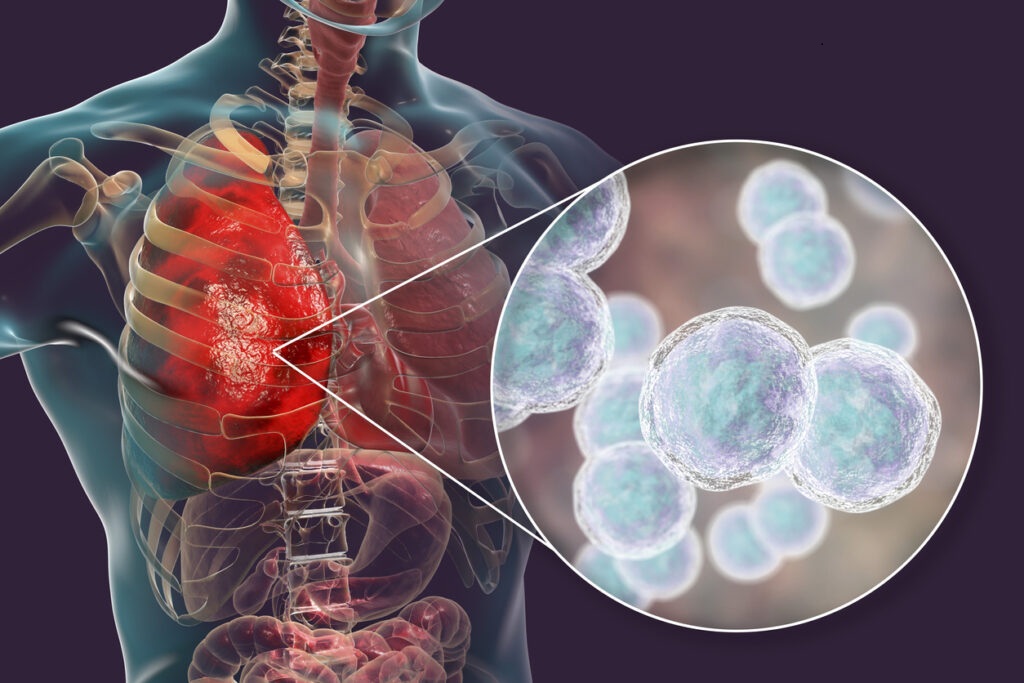

Într-un studiu recent realizat de cercetătorii de la Universitatea din Leipzig, Germania, un extract natural din iarbă mare (Inula helenium) a fost evidențiat pentru capacitatea sa de a susține regenerarea țesutului pulmonar, mai ales după infecții respiratorii sau expunere prelungită la poluanți. Planta, cunoscută în medicina tradițională europeană de secole, revine în atenția științifică datorită compușilor activi cu acțiune reparatoare și expectorantă.

Cercetătorii au publicat în European Journal of Medicinal Plants (2024) că elecampanul (iarba mare) conține lactone sesquiterpenice și alantolactonă, substanțe care:

- stimulează regenerarea celulelor epiteliale pulmonare deteriorate

- reduc inflamația cronică la nivelul bronhiilor

- împiedică dezvoltarea fibrozei pulmonare

Efectele au fost observate atât in vitro, cât și în testări pe modele animale expuse la agenți iritanți sau fum de țigară.

🌬️ Cum acționează extractul asupra plămânilor

✔️ Calmează tusea uscată sau productivă

✔️ Reduce inflamația căilor respiratorii

✔️ Favorizează eliminarea mucusului acumulat

✔️ Protejează și ajută la refacerea mucoasei bronșice

✔️ Susține oxigenarea mai eficientă a organismului